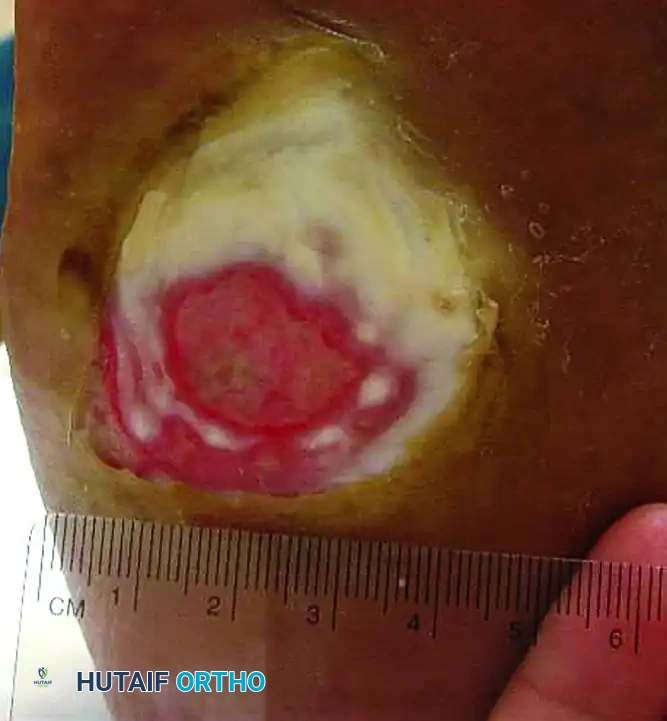

Superficial (Wagner Grade 1) ulcer. The dermis is breached, but deep structures are not exposed.

Deep (Wagner Grade 2) ulcer with exposed tendon and joint capsule. Immediate offloading and infection surveillance are required.

Wagner Grade 3 ulcer with underlying osteomyelitis. Note the deep tissue destruction and purulent exudate.